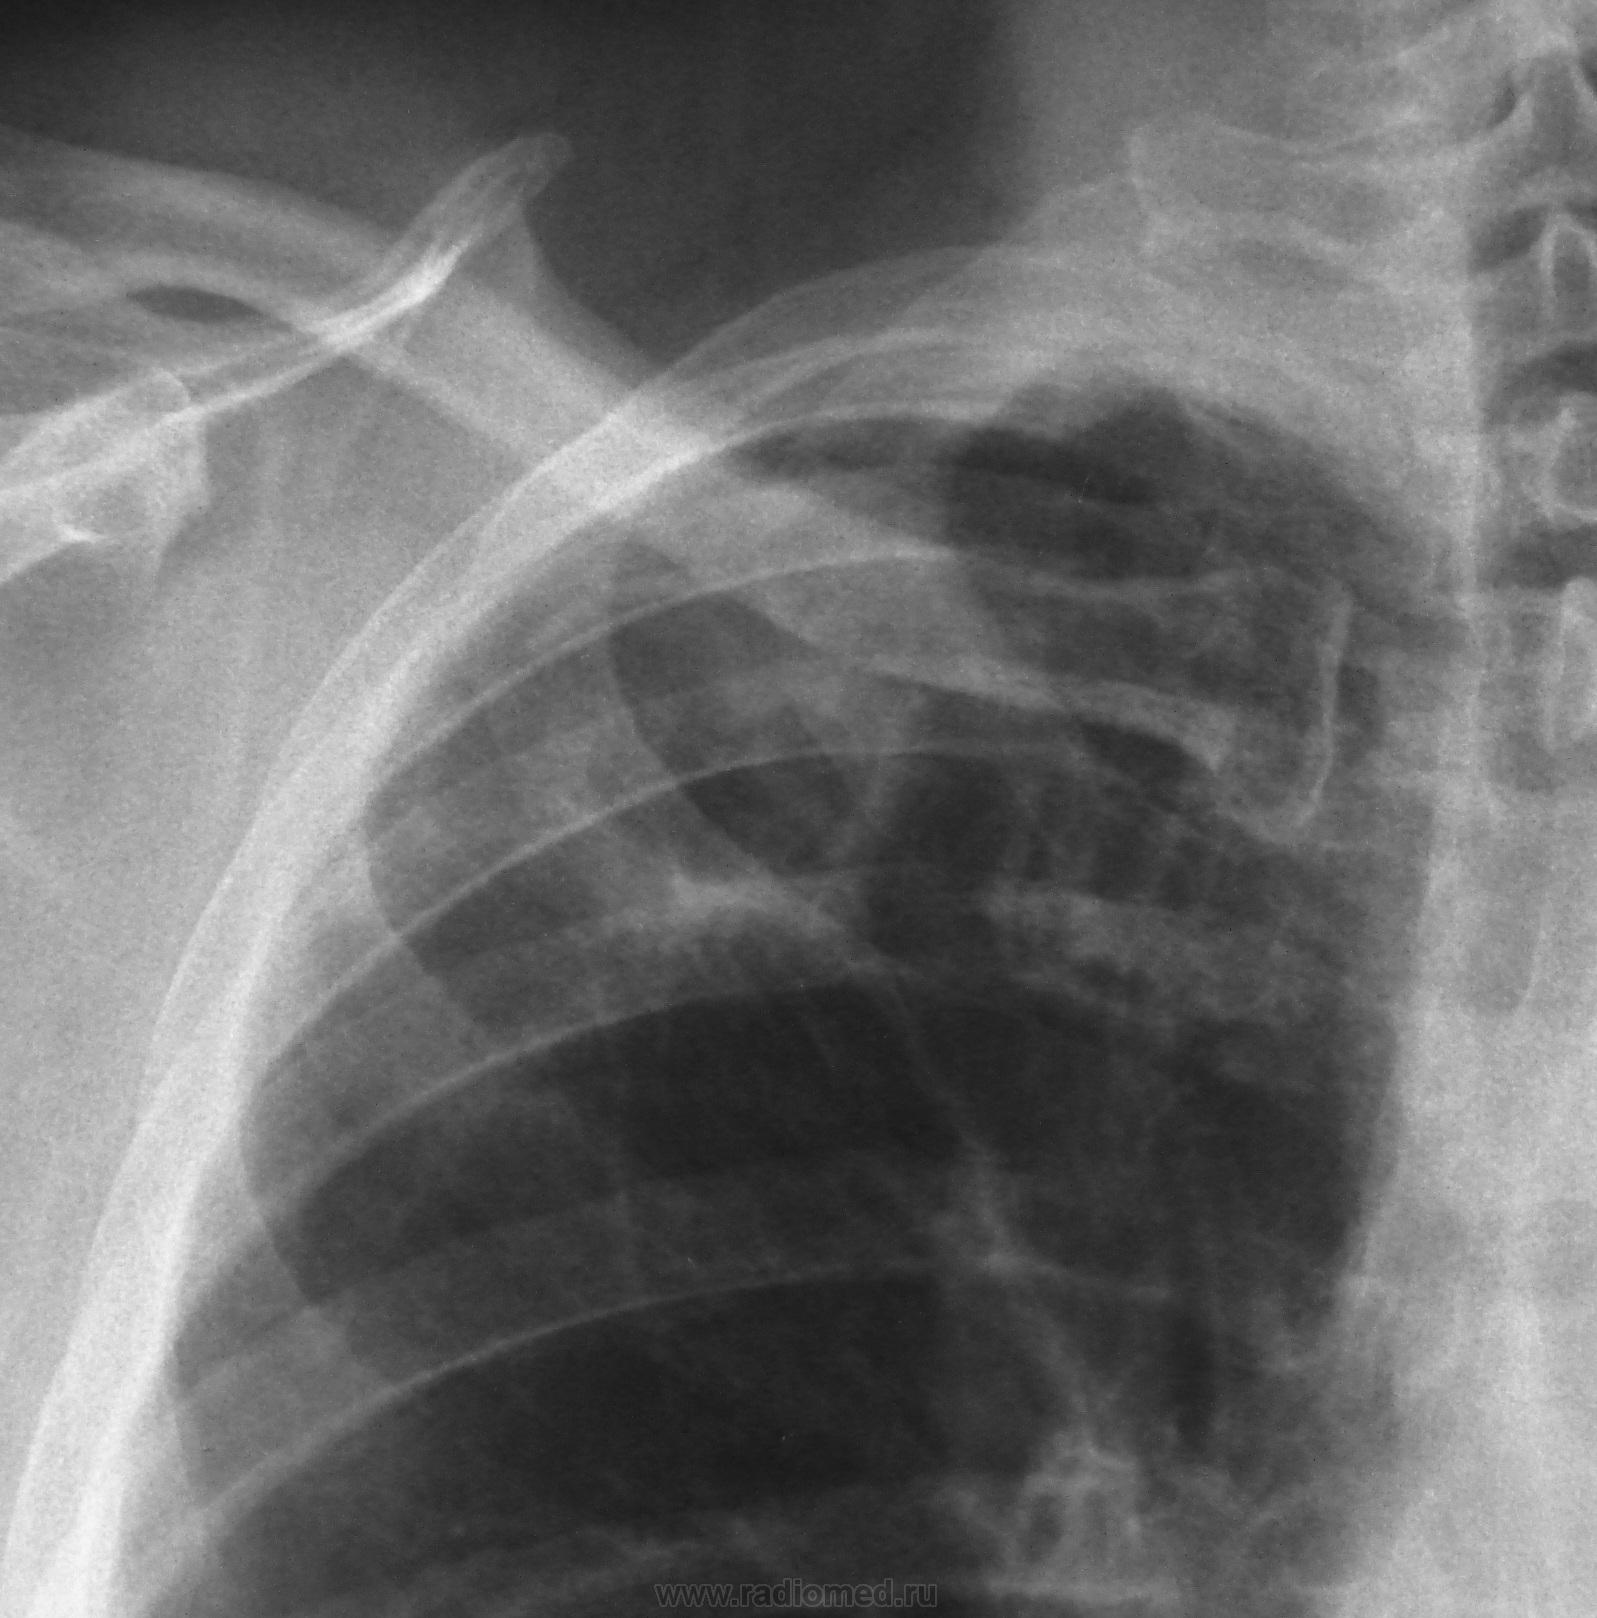

67 л. Вич-отрицательный. Пенсионер. Проведена проверочная флюорография перед операцией на коленном суставе. Флюорография в 2010 г. На контроль не вызывали. Архива нет. Кл. анализ крови - норма. Поликлиника намерена срочно направить в ПТД. Жду Ваших мнений коллеги. Nikolas.

Толстые стенки образования, центральный характер распада, нежная дорожка к корню, я предположил бы периферический рак с распадом, да и возраст к этому располагает. Дифференцировать с туберкуломой, с распадом.

Думаю сначала следует исключить кавернозный тбс учитывая локализацию и фиброзные изменения. Хотя по характеру полости и стенок больше за рак действительно. Но тут нехватает выраженой лимфоаденопатии корня...В общем случай достаточно сложный для диф.диагностики по рентгену. По традиции на первое место поставлю рак с распадом. Обосную отсутствием изменений кл.ан. крови.

Выскажусь,почему написала о кавернизирующейся туберкуломе: 1.ОАК-без особенностей 2.плевро-апикальные наложения на стороне поражения. 3очаги отсева рядом и нельзя исключить их наличие в цирротически измененной ср/доле(без тмг). 4характер полости деструкции. 5наличие "дорожки"к корню.Хотя,ее вид может соответствовать и раковому лимфангоиту. 6плевро-диафр.спайки,без которых не бывает инфильтративного tbc,а с-r может быть

Думаю каверна из туберкуломы.Фирозный усик к висцеральной плевре,результат затихшего ангоит\По верхнему контуру есть участок равномерной толщины.В месте бронхососудистого примыкания разрыв контура.(это не должно быть при раке).Томограммы не визуализирут бронх ,но он там есть.

Происходит кавернизация туберкуломы в S2 верхней доли правого легкого